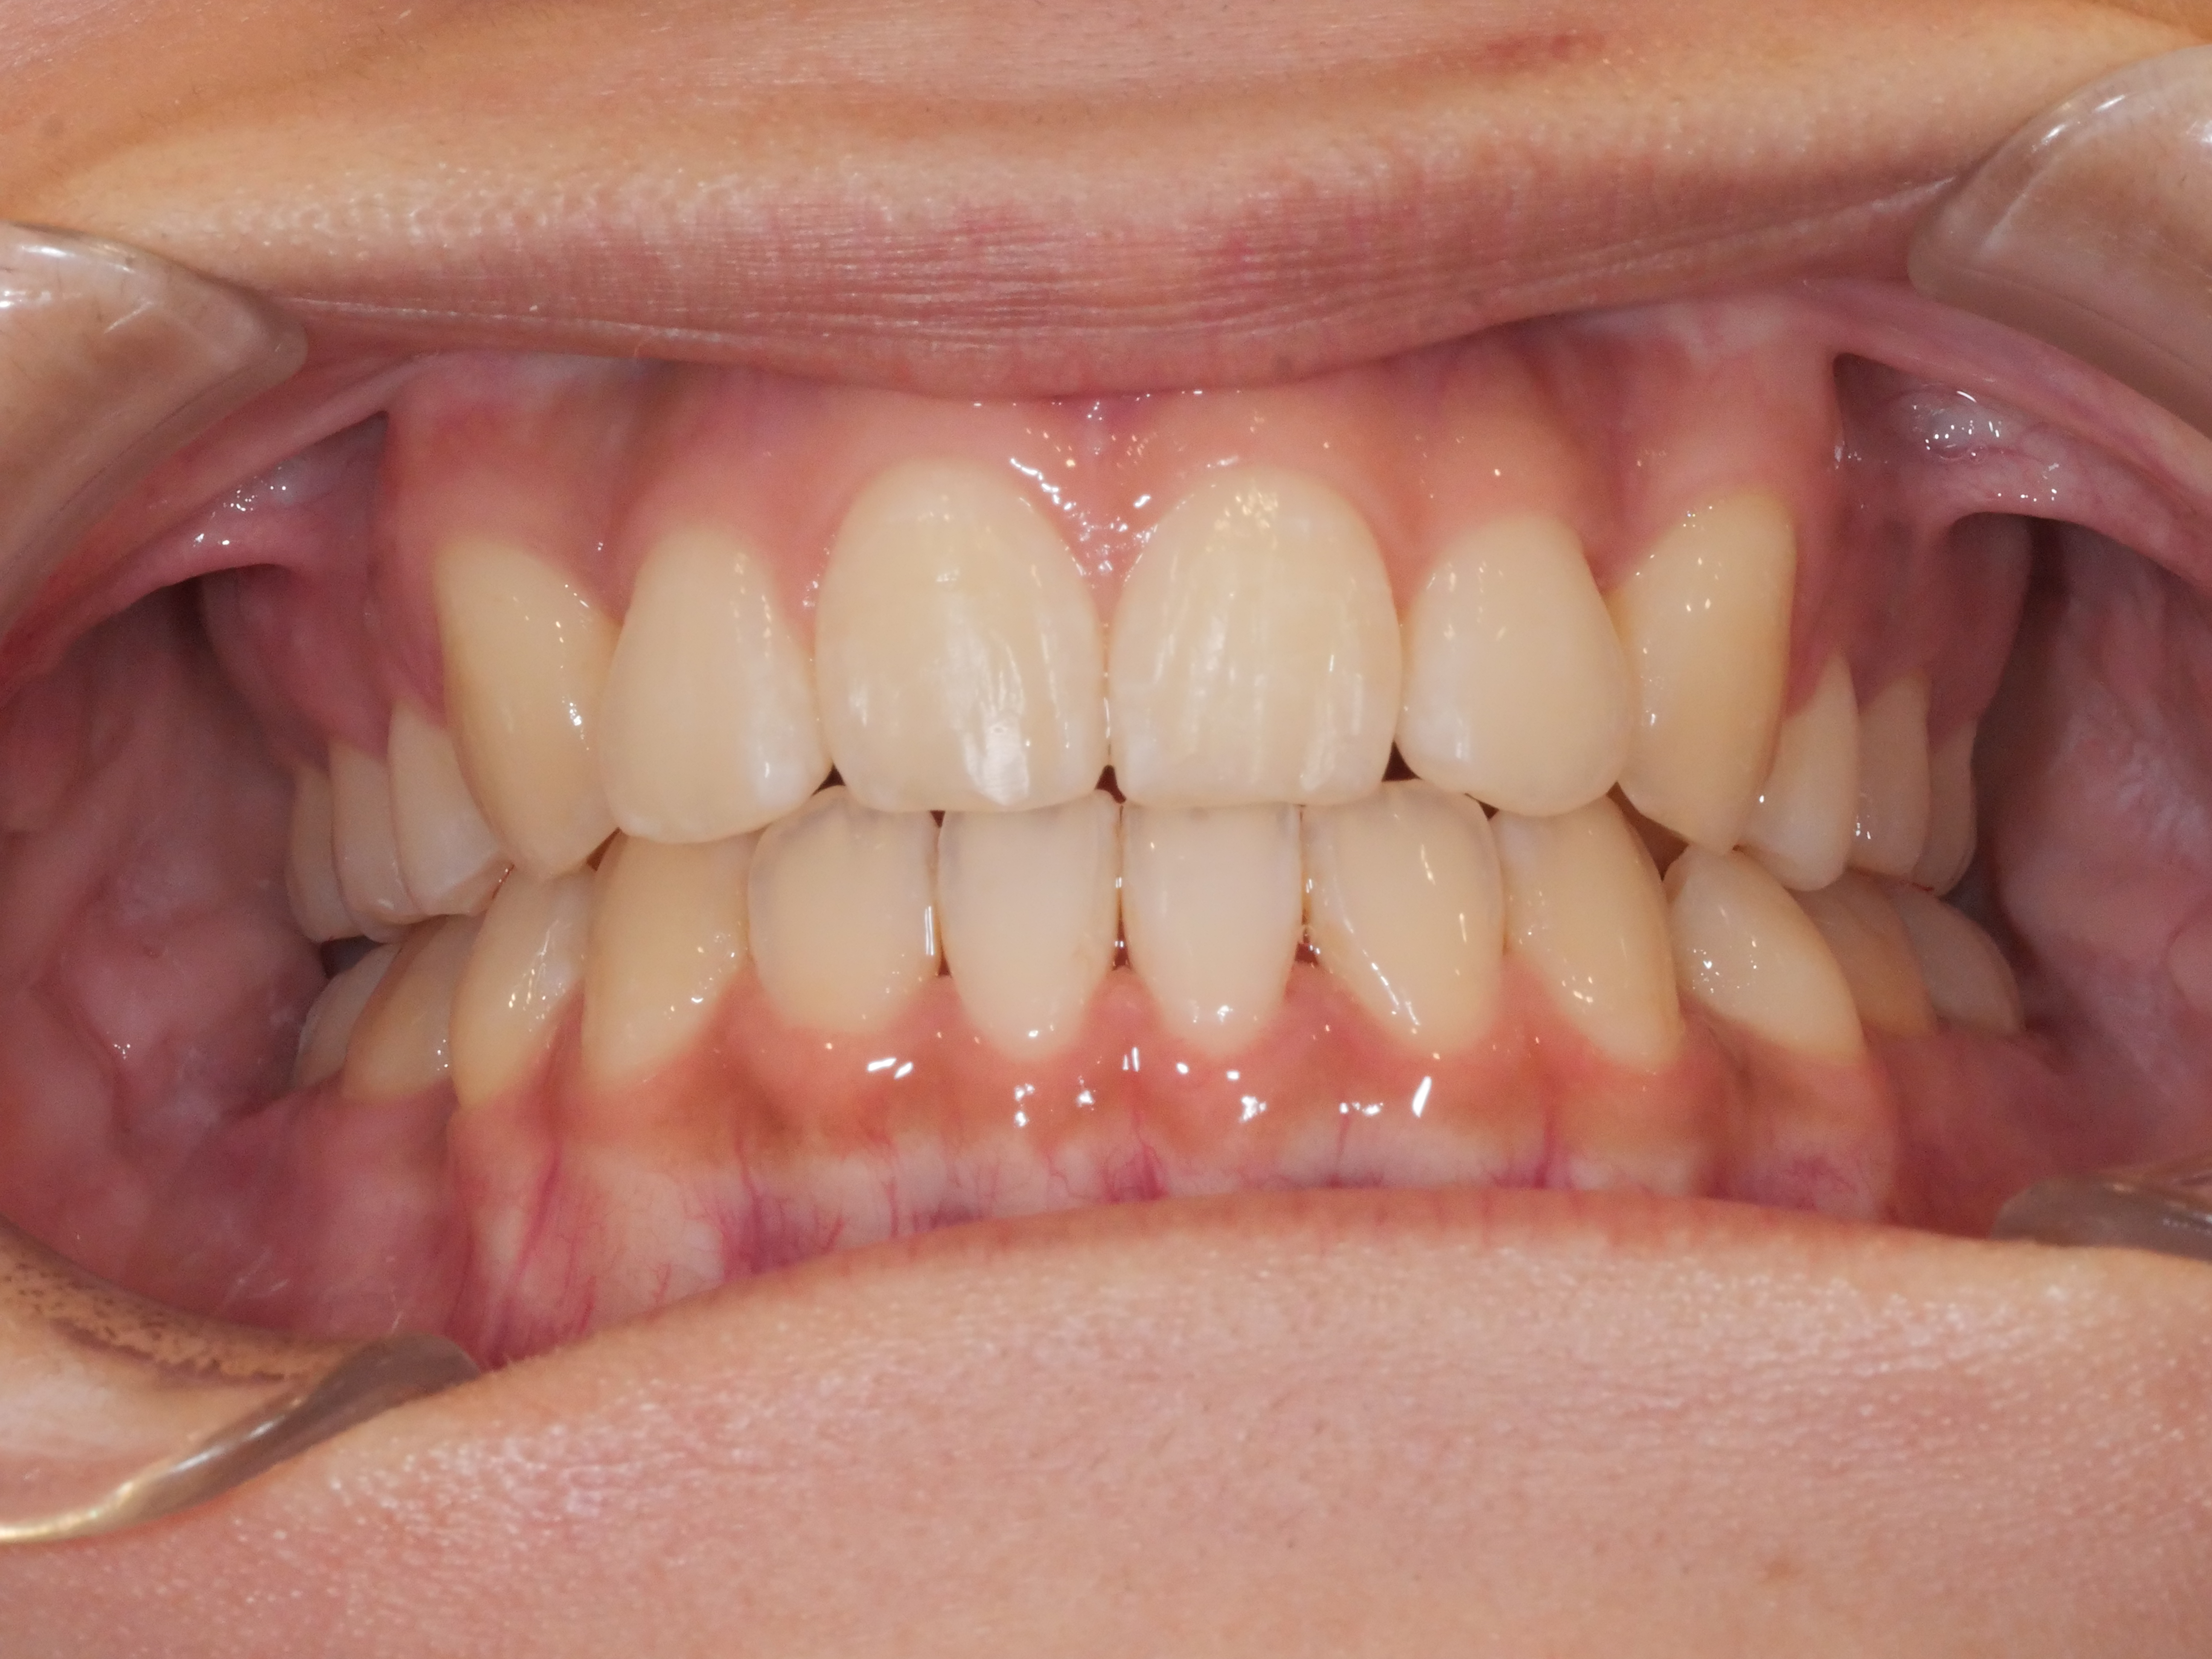

before

after

八重歯(ガチャ歯)を治したい

歯列が狭い・かみ合わせと凸凹

主訴 【主訴】凸凹を治したい・上の歯が出ている 【診断・症状】叢生・交叉咬合

治療費用 検査・診断:38,500-/裏側矯正治療:1,375,000-(※全て税込)

治療期間 約2年3(24回)

抜歯 抜歯:有(上4,4)

矯正の装置 裏側矯正(舌側矯正)+QH

副作用、リスク 歯肉退縮・歯根吸収・疼痛・咬合の違和感・装置の違和感